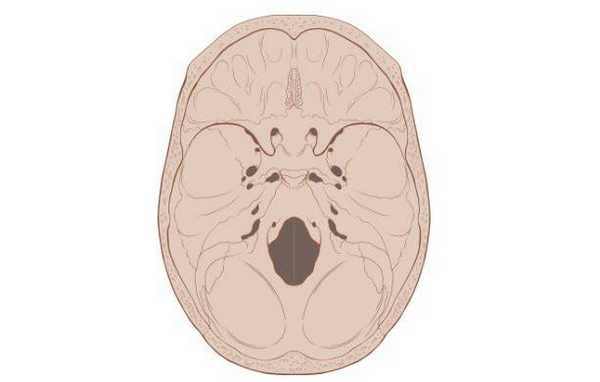

Схематическое изображение основания черепа

Основание черепа - область, образуемая затылочной, височными, решетчатой, лобной и клиновидной костями. Внутренняя поверхность данной анатомической структуры играет роль площадки, на которой покоится головной мозг. Через большое отверстие затылочной кости проходит ствол мозга. Наружная поверхность основания черепа богата нервными волокнами, кровеносными сосудами, связками и сухожилиями.

Основание черепа: вид изнутри и снизу